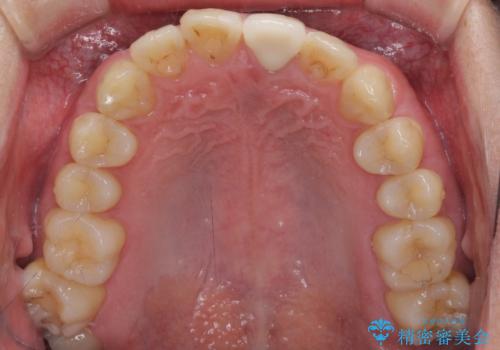

歯髄は既に壊死していたため、根管治療を行い、その後オールセラミッククラウンにて補綴することとしました。

変色による周囲に視線が気にならなくなり、明るいくらいとなりました。